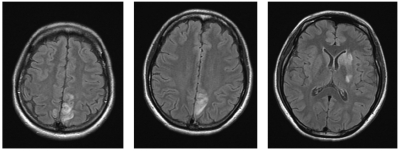

意識レベルは JCSⅠ-1。心拍数 90/分、整。血圧 190/120 mmHg。呼吸数 16/分。SpO2 97 %(room air)。全身に浮腫を認める。尿所見:蛋白3+。硫酸マグネシウムの持続静注を開始した後に撮影された頭部MRI の FLAIR 像を別に示す。